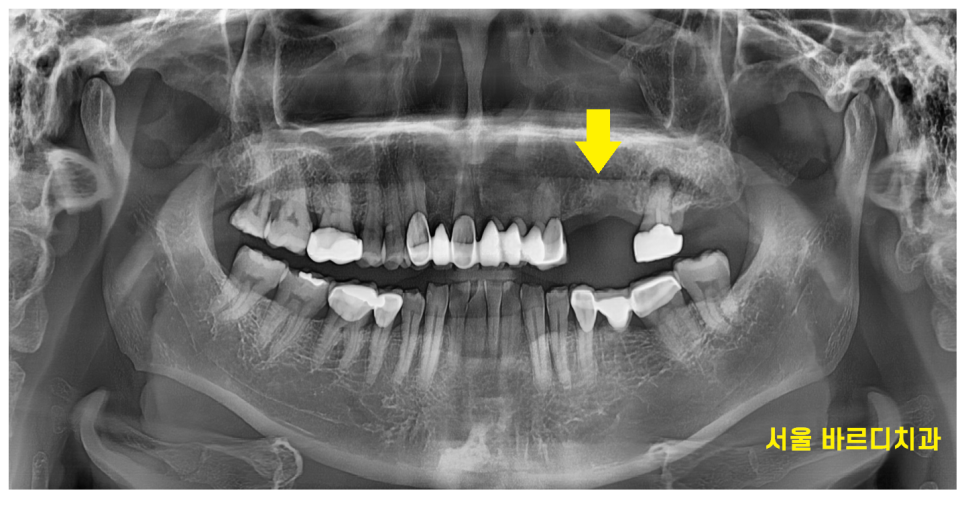

임플란트는 치아를 발치한 뒤 즉시 식립할 수도 있지만,

어떤 환자분께는 몇달씩 기다려야할 수 있습니다.

치아에 염증이 심해 발치 후 뼈이식만 먼저 하고 기다리거나

발치 후 공백 상태로 있으면 다음과 같은 문제가 발생할 수 있습니다

치아 이동

심미적 이유

식사를 위해

먼저 치아 이동 부터 설명드리겠습니다.

딱딱딱 맞물리던 치아들이 한쪽이 없어지면

없어진 쪽으로 이동을 시작합니다.

이렇게 되면 나중에 임플란트를 하고 싶어도

높이가 안나오거나

움직인 치아를 깎아서 치아 높이를 맞춰줘야합니다.